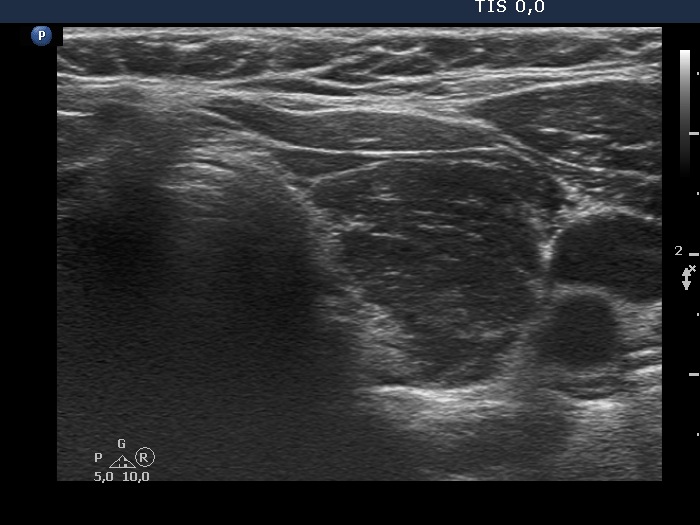

Discrete lesion or nodule in Hashimoto's thyroiditis - case 35 (61) (ultrasonographic picture 4)

Lower part of the left lobe, transverse view. The pattern is identical to that seen in the right lobe.